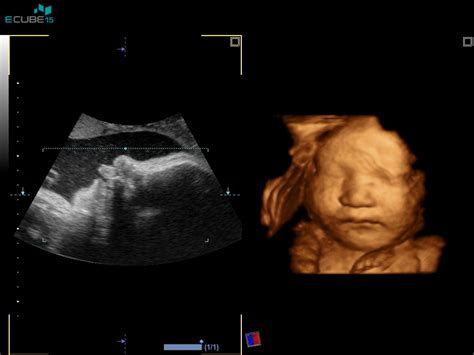

Ultrazvočne preiskave so nepogrešljivo orodje v spremljanju nosečnosti. Prva ultrazvočna preiskava se opravi med 8. in 12. tednom nosečnosti, s čimer se potrdi intrauterina nosečnost, določi število plodov in oceni vitalnost ter določi predvideni datum poroda.

Natančna ultrazvočna ocena morfologije ploda, ki je ena najpomembnejših preiskav, se običajno opravi med 20. in 22. tednom nosečnosti. Namenjena je odkrivanju večjih razvojnih nepravilnosti ter t.i. mehkih označevalcev, ki lahko povečajo tveganje za kromosomske napake. V tem času je razvoj plodovih organov večinoma že zaključen, kar omogoča z veliko verjetnostjo napoved rojstva zdravega otroka. Dodatne ultrazvočne preiskave se lahko opravijo v 32. tednu za oceno rasti ploda, ter med 35. in 37. tednom, ko se ocenjuje tudi količina plodovnice, lega ploda in predvidena teža ob porodu.